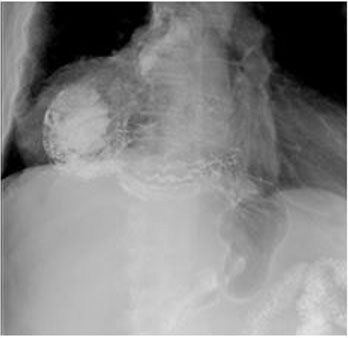

We provide a commented surgical video (Video 1 ) to describe this surgical procedure. The patient went through a quick recovery. The upper gastrointestinal series on postoperative day 2 detected no recurrence nor sign of dysphagia (Figure 3). The patient was discharged on the third day after the intervention. The Dindo-Clavien classification was I.

Figure 3: Upper gastrointestinal series with oral intake of contrast, postoperative exam.